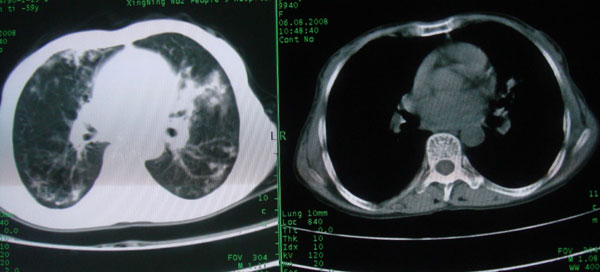

考虑支气管扩张并感染

1慢支伴感染;右下肺周围型肺癌。

1\\慢支并感染

2\\浸润型肺结核

本例应该是“慢性疾病并发多种合并症”即:慢支并感染并支气管扩张征!结合病灶分布 形态分析,不除外合并“继发性肺结核”!